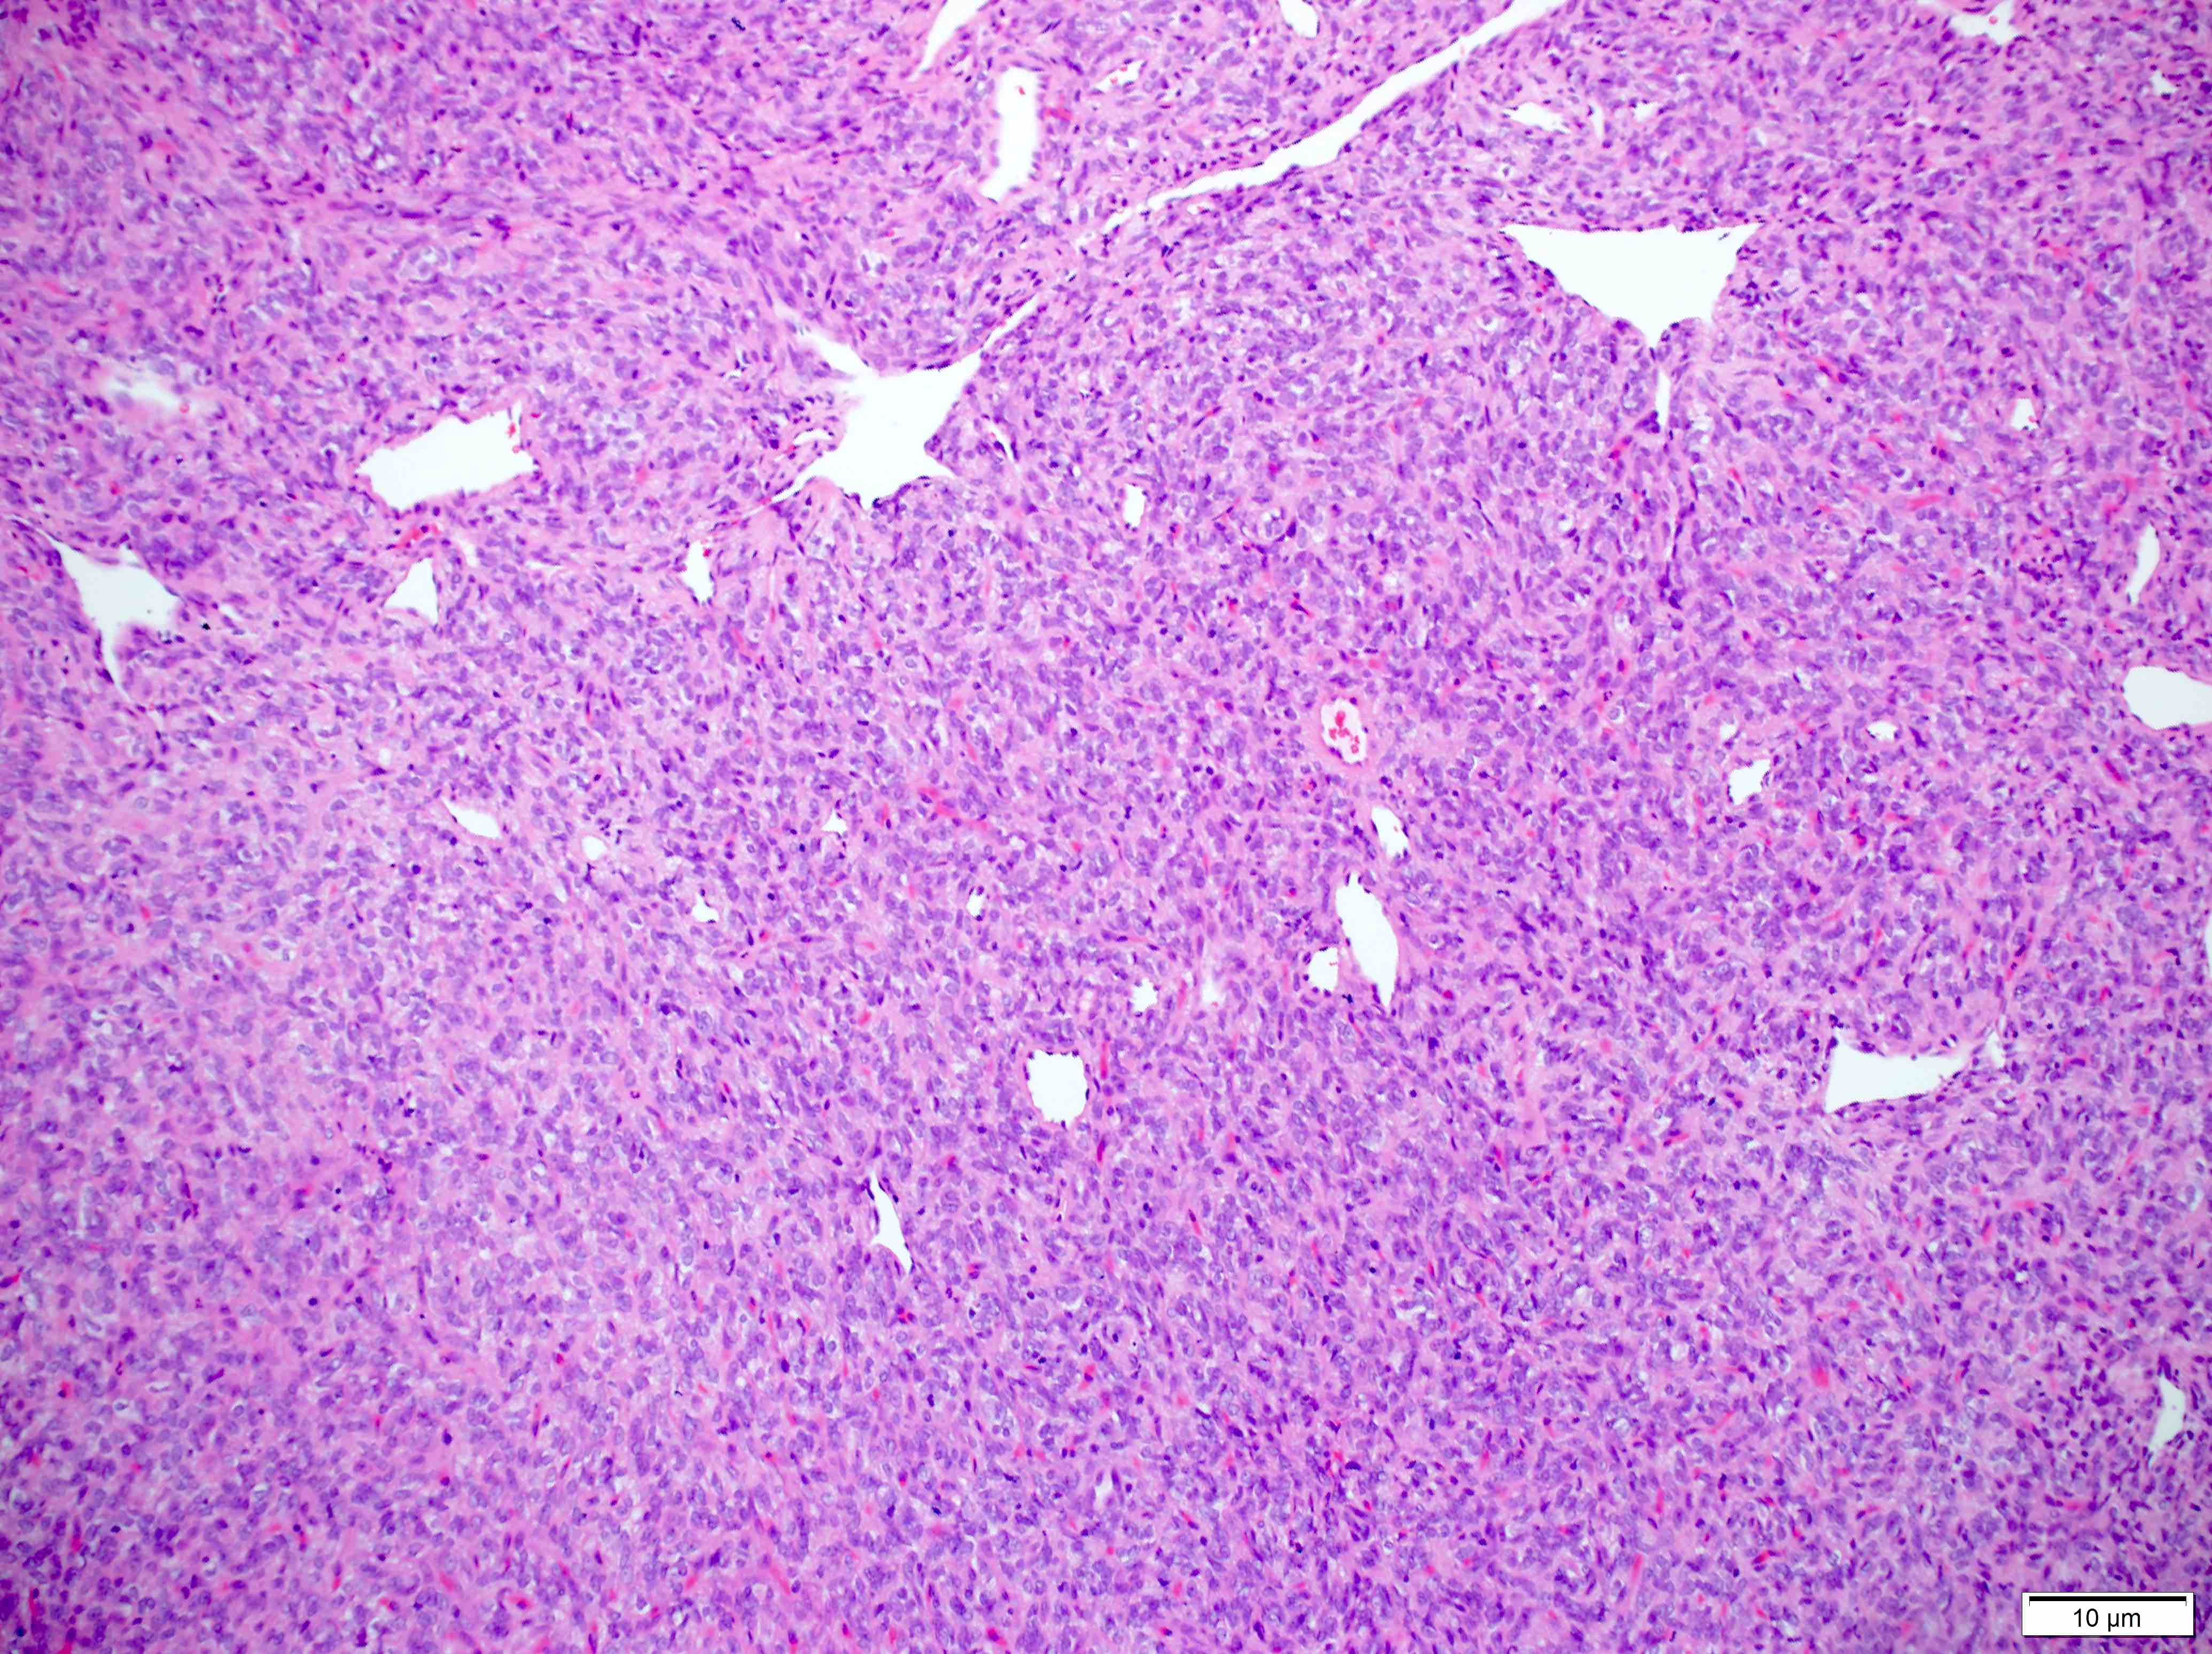

Microscopic (histologic) description

- Essential: patternless pattern of spindle cells, often solid but can also have papillary and other architectures, arranged around branching hyalinized vessels

- Varying amounts of stromal collagen and overall cellularity

- Nuclei are bland, without features seen in mimicking neoplasms

- Often has staghorn vasculature

Microscopic (histologic) images